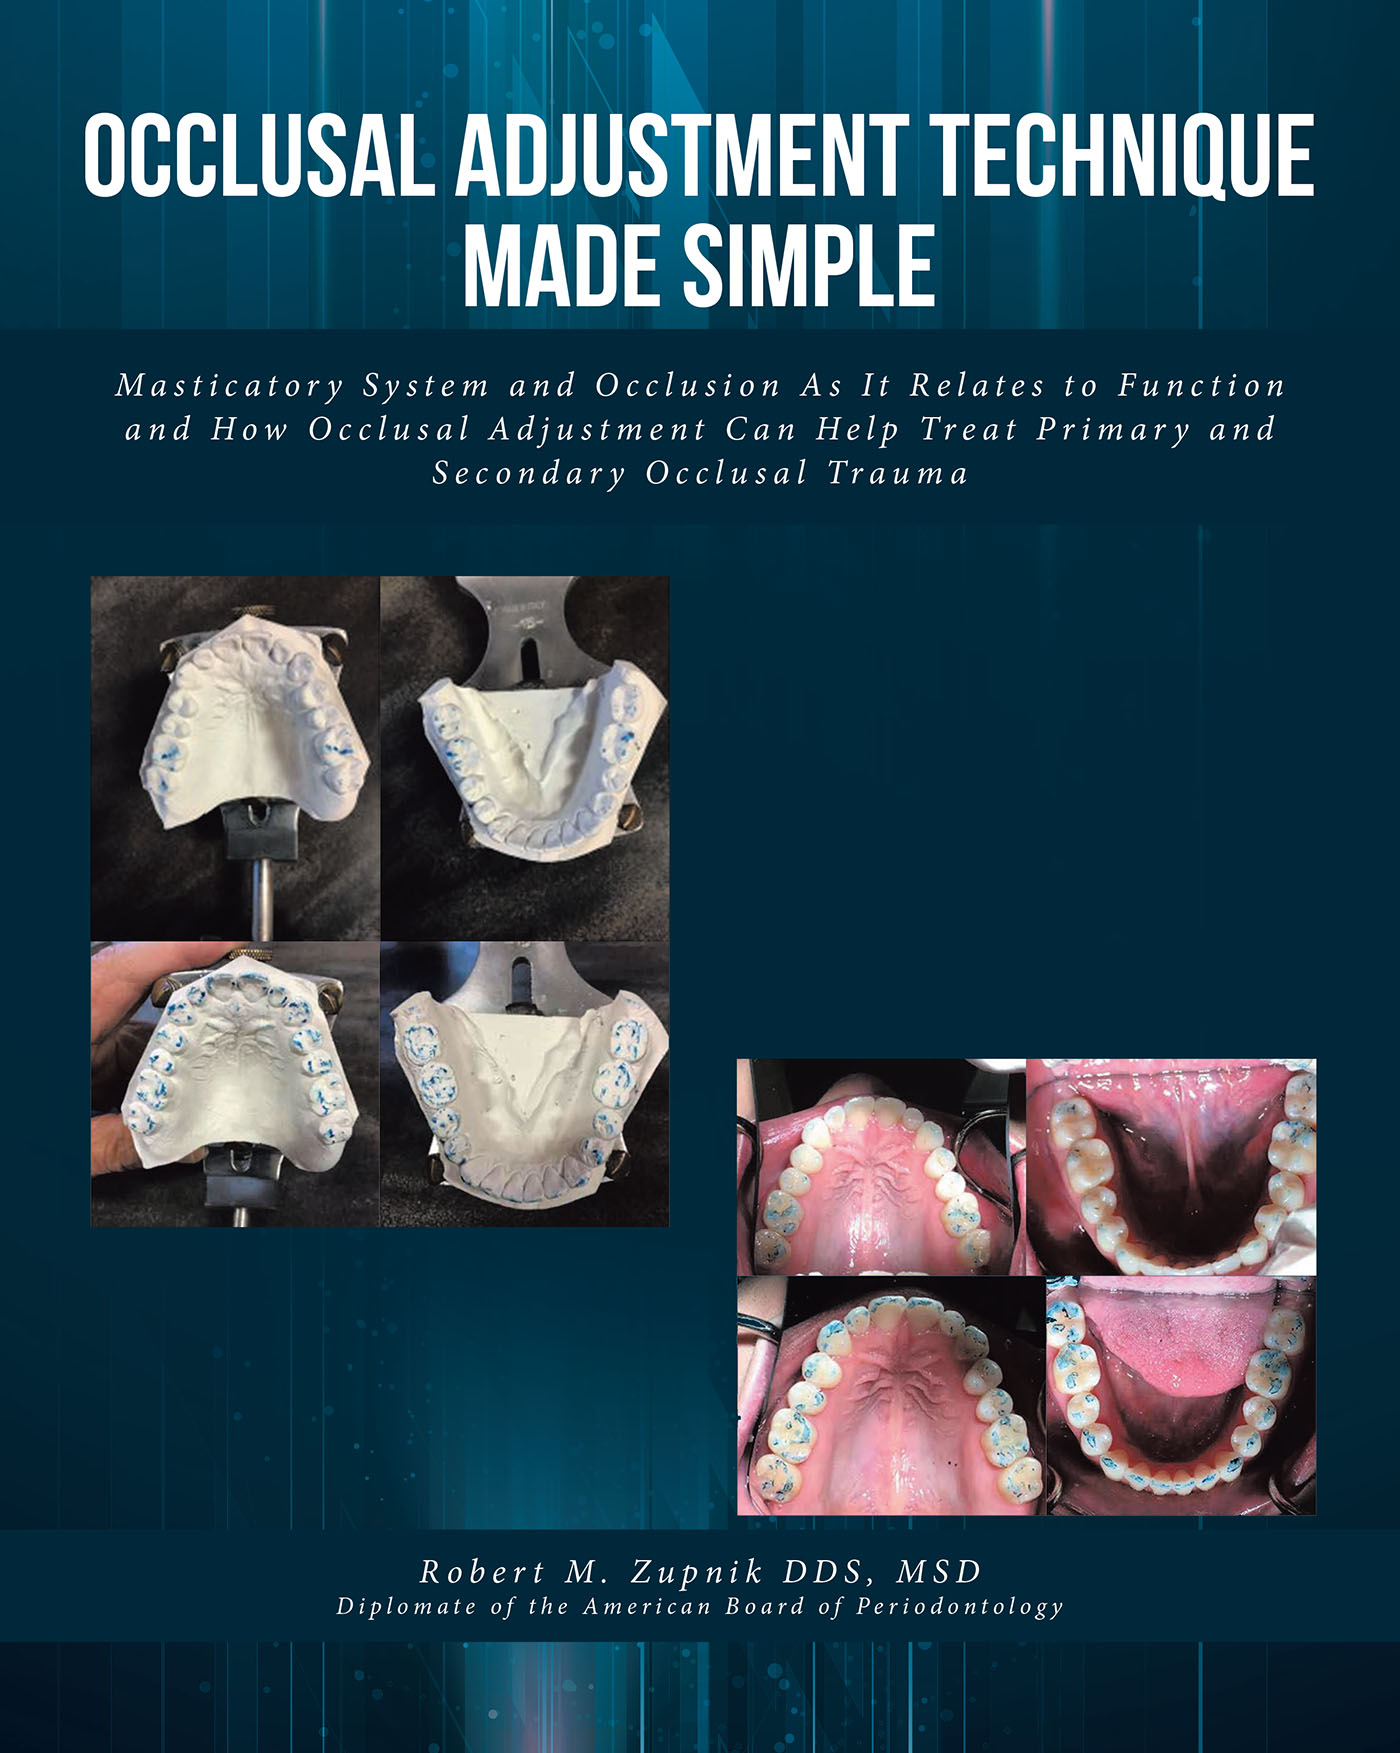

RESTORATIVE DESIGN & PRACTICAL OCCLUSIO… RESTORATIVE DESIGN & PRACTICAL OCCLUSIO… Robert M. Zupnikの詳細情報

RESTORATIVE DESIGN & PRACTICAL OCCLUSIO… Robert M. Zupnik。RESTORATIVE DESIGN & PRACTICAL OCCLUSIO… Robert M. Zupnik。Reficio™ 100 Advanced DBM Fiber Putty Syringe, Curved - 1.0。「RESTORATIVE DESIGN & PRACTICAL OCCLUSION 実践的咬合」本多 正明定価: ¥ 330001年ほど前に新品購入し、一度読んで本棚に並べていました。。Functional Occlusion in Restorative Dentistry and。カバーやケースに多少の傷やスレはありますが、通読に支障をきたすような汚れや破れなどはありません。#本多正明 #本多_正明 #本 #自然/医療・薬学・健康